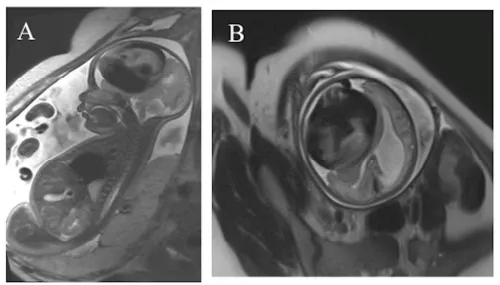

胎儿MRI进一步显示右侧大脑半球巨大血管病变,压迫邻近脑实质,导致中线结构向对侧移位,并已出现早期梗阻性脑积水(图1A-B)。

出生第1天,亨利被确认存在颅内血管病变,表现为囊状动脉瘤样结构,内部为搏动性血流。同日进行的磁共振血管成像(MRA)显示右侧额叶软脑膜动静脉瘘(PAVF),伴软脑膜静脉瘤样扩张,其内血流湍急,经扩张静脉引流入上矢状窦(图1C-E)。该病变还压迫同侧脑组织,导致局部脑实质萎缩。